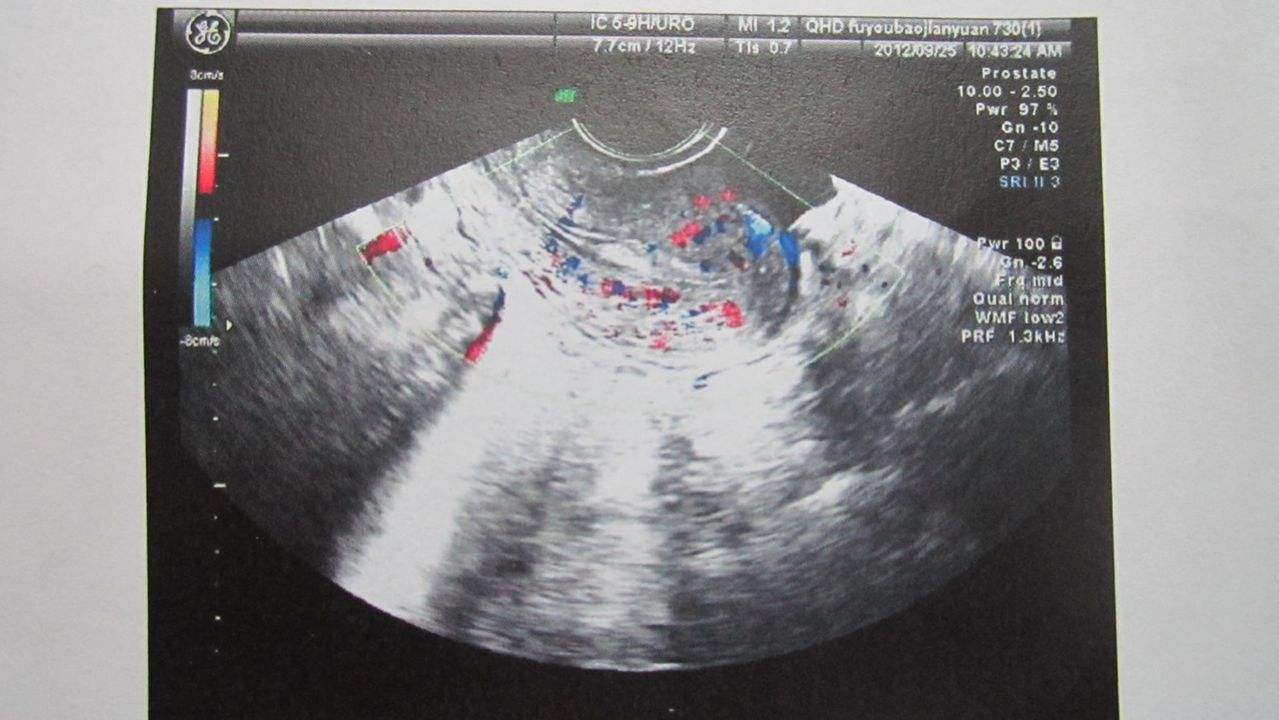

其实阴超与B超都是属于超声检查的一种,只不过B超要憋尿,在体外检查,而阴超,就要把探头放到阴道内做检查。阴超不仅可以检查胎儿,还能检查到女性的子宫,卵巢等生殖器。而且准确率也更高,图像更清晰等。

不过做阴超的时候,女性一般都会特别紧张,毕竟要把探头放进引导内啊,还要在肚子里面看来看去的。不过别担心,医生也会有相应的润滑剂,不会在干涩中导致女性疼痛的。这项检查也非常成熟,一般是在阴道内的4-5厘米地方检查,这个地方是不会对胎儿有什么影响的。

做阴超的话,一般在怀孕初期B超还检测不到胎心胎芽的时候,就可以尝试做阴超了,毕竟阴超比B超早一周可以发现胎心胎压的情况。还能知道孕周哦。再者,如果孕早期出现腹痛或者持续出血的情况,也要做阴超检查一下。毕竟这个时候很可能是流产前兆或者宫外孕。